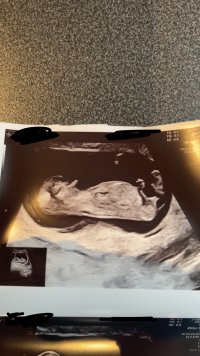

Hei! Nylig vært på tidlig offentlig ultralyd. Hvor jordmor tippet på jente, men kunne ikke garantere. Noen som tørr å gjette?